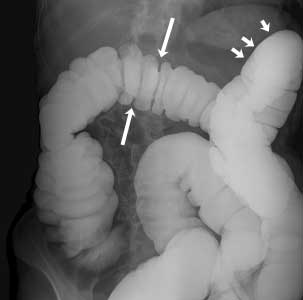

Normal Barium Enema